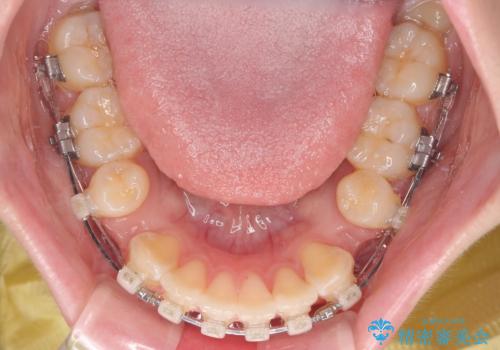

- 矯正装置

- クリアブラケット

- 治療期間

- 1年8ヶ月

- くちばしのように飛び出した前歯を気にして来院された患者様です。

上下左右の第一小臼歯4本を抜歯して、ワイヤー装置にて矯正治療を行うこととしました。